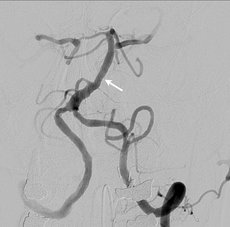

Behandlung einer Engstelle der A. basilaris